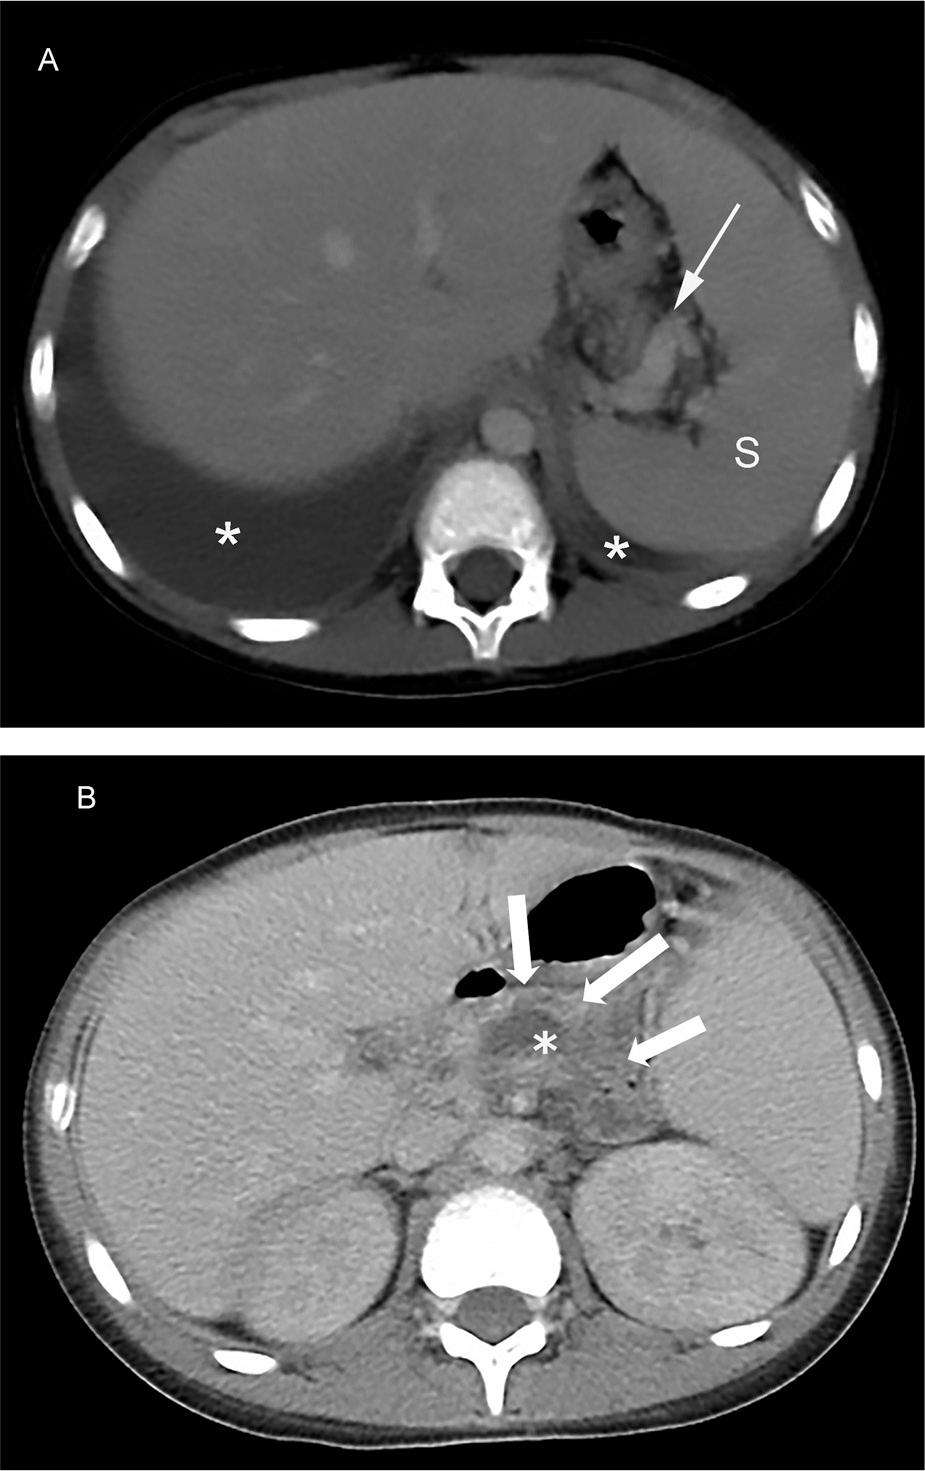

Figure 2